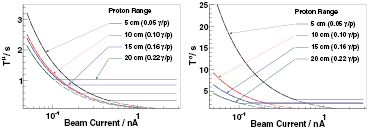

4.4.3. Time requirements for range verification.

So far, the presented results restrict the analysis of prompt γ-rays detected within a narrow energy ROI (All4440, SE). However, in order to receive fast but reliable range information based on reliable measurement statistics, it is reasonable to utilize an increased energy ROI of detected γ-rays. In the performed Geant4 simulations the resulting integral emission rates Γγ have a value of 0.05 up to 0.25 prompt γ-rays per proton at a proton range of R = 2 cm and R = 27 cm respectively. Here a prompt γ-ray emission energy Eγ of at least 1 MeV is assumed. With an increased energy ROI of the emitted prompt γ-rays the resulting simulated profiles gx resemble the box profile. This is in good agreement with data reported by Biegun et al (2012).

We estimate for a reasonable scintillator-based detection system according to the setup given in figure 5. The detector may have size of ∅2'' × 2''. We propose a fast scintillating material such as LaBr3 with a photon detection efficiency εD, which can be derived by assuming the minimum photon interaction cross-section for the given scintillator (NIST 2014), thus εD = 0.4. Note, that εD is the minimum absolute detection efficiency, i.e. the probability that a photon interacts in the detector by any type of interaction. This is valid since the timing information of an interacting prompt γ-ray is valid, even if it is not completely absorbed. The detector is situated at d = 30 cm distance of the beam target entrance (figure 5). Figure 13 shows the required measurement times Tμ and Tσ to reach the precision of the proton range  mm as a function of the beam current at the irradiated target. The respective integral emission rate Γγ is given within the brackets in the graph. All the curves show a plateau at a beam current of about 100 pA or higher. This is due to the assumed maximum of the detectable throughput of the data acquisition system which limits the detection rate to 105 cps. The continuous dashed lines represent systems with (hypothetical) unlimited throughput. Figure 13 shows, that the required measurement times are mainly limited by the detector throughput, especially at therapeutic relevant beam currents of ≈1 nA. This even applies, if the overestimation of prompt γ-ray yields by the Geant4 simulations is wrong by factor of two. The selected maximum detector throughput is a real system throughput based on a commercial digital spectrometer, i.e. the electronic data acquisition is capable of processing the event rate supplied by the detector. Modern designs based on digital pulse processing may even allow up to 106 cps system throughput.

mm as a function of the beam current at the irradiated target. The respective integral emission rate Γγ is given within the brackets in the graph. All the curves show a plateau at a beam current of about 100 pA or higher. This is due to the assumed maximum of the detectable throughput of the data acquisition system which limits the detection rate to 105 cps. The continuous dashed lines represent systems with (hypothetical) unlimited throughput. Figure 13 shows, that the required measurement times are mainly limited by the detector throughput, especially at therapeutic relevant beam currents of ≈1 nA. This even applies, if the overestimation of prompt γ-ray yields by the Geant4 simulations is wrong by factor of two. The selected maximum detector throughput is a real system throughput based on a commercial digital spectrometer, i.e. the electronic data acquisition is capable of processing the event rate supplied by the detector. Modern designs based on digital pulse processing may even allow up to 106 cps system throughput.

Figure 13. Required measurement times Tμ (left, (11)) and Tσ (right, (12)) to reach a proton range uncertainty  mm based on a PGT detector system comparable to figure 5. The integral prompt γ-ray emission rate Γγ per proton is given within the legend of the graph. Setup constraints are discussed in the text. The assumed system time resolution σΣ is 450 ps.

mm based on a PGT detector system comparable to figure 5. The integral prompt γ-ray emission rate Γγ per proton is given within the legend of the graph. Setup constraints are discussed in the text. The assumed system time resolution σΣ is 450 ps.

Download figure: